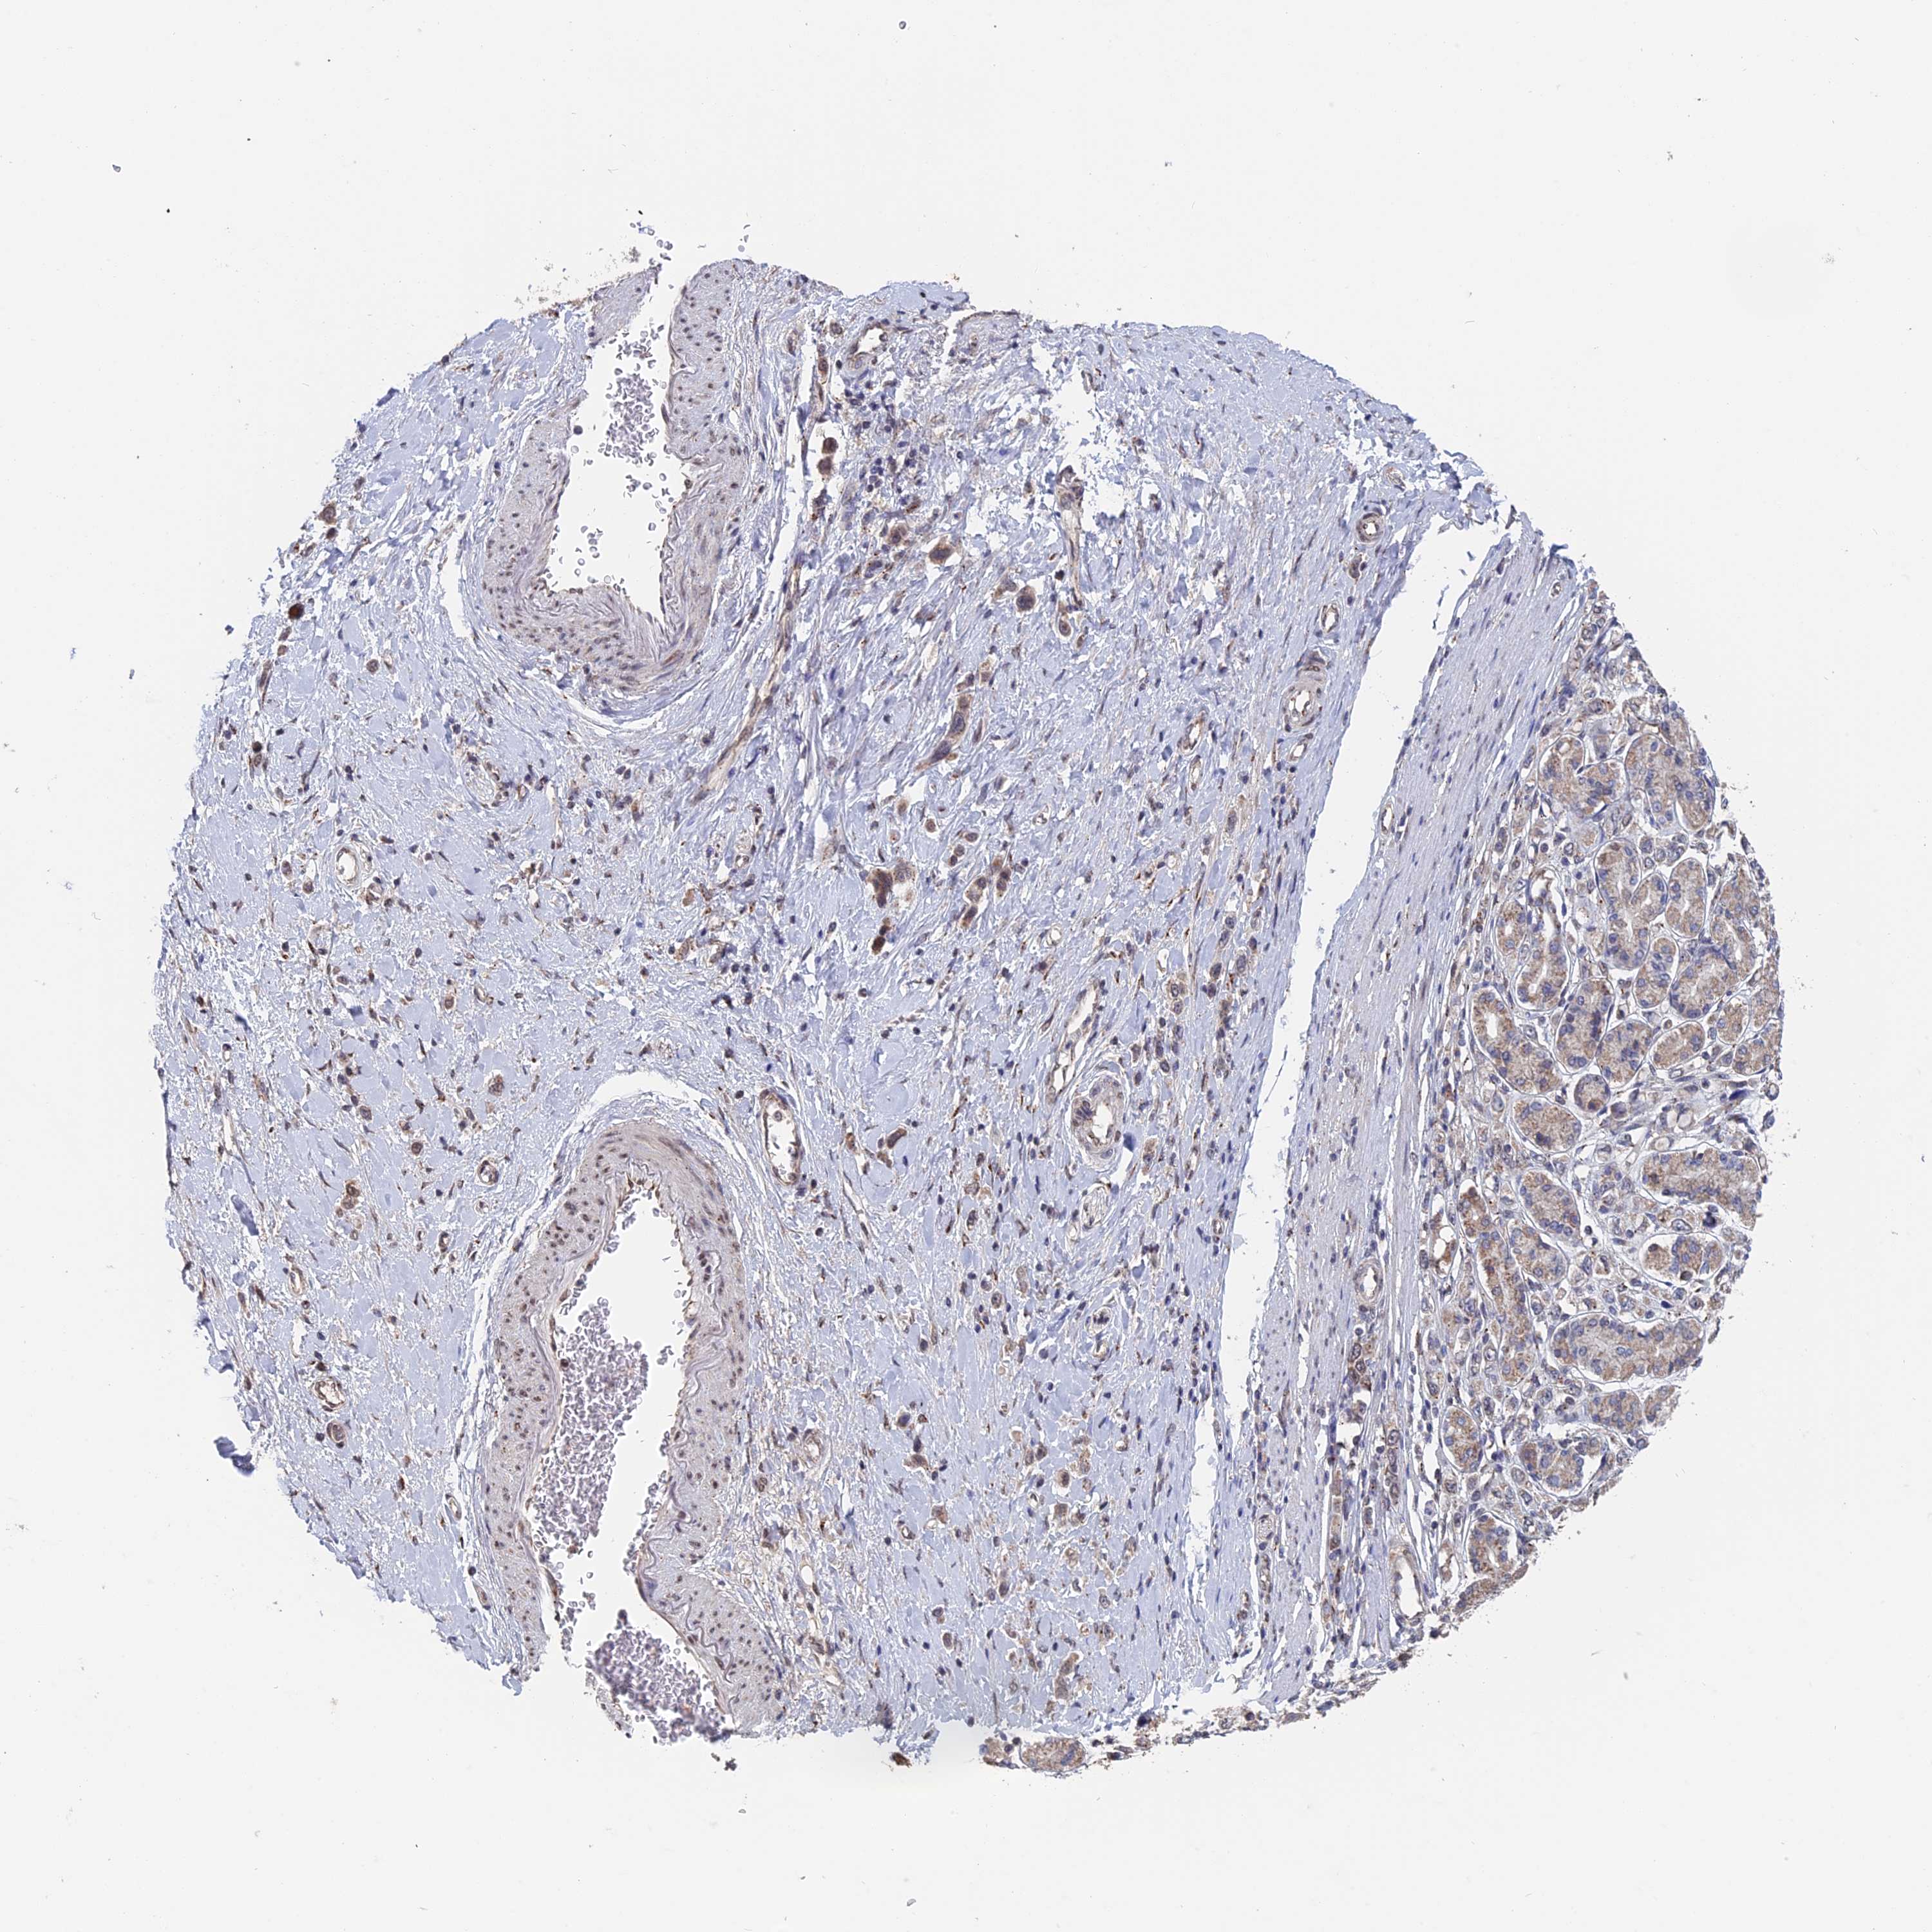

STOMACH CANCER - Protein expressioni

A mouse-over function shows sample information and annotation data. Click on an image to view it in a full screen mode. Samples can be filtered based on level of antibody staining by selecting one or several of the following categories: high, medium, low and not detected. The assay and annotation is described here.

Note that samples used for immunohistochemistry by the Human Protein Atlas do not correspond to samples in the TCGA dataset.

Antibody stainingi

Antibody staining in the annotated cell types in the current human tissue is reported as not detected, low, medium, or high, based on conventional immunohistochemistry profiling in selected tissues. This score is based on the combination of the staining intensity and fraction of stained cells.

Each image is clickable and will lead to virtual microscopy that enables deeper exploration of all samples and also displays staining intensity scores, fraction scores and subcellular localization as well as patient and tissue information for each sample.

Antibody HPA039105

Antibody HPA039828

Staining

High

Medium

Low

Not detected

Intensity

Strong

Moderate

Weak

Negative

Quantity

>75%

75%-25%

<25%

None

Location

Nuclear

Cytoplasmic/membranous

Cytoplasmic/membranous,nuclear

Adenocarcinoma, NOS